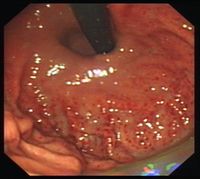

- 急性刺激胃炎,又称单纯性胃炎英文为acute irritated gastritis多因暴饮暴食、食用过热、刺激性或烈性酒所致,胃镜可见胃粘膜潮红、充血、水肿、有粘液附着,有时可见糜烂;

- 急性出血性胃炎英文为acute hemorrhagic gastritis多由服药不当或过度酗酒所致,或创伤、手术等应激反应所致;胃镜可见胃粘膜急性出血并轻度糜烂、或可见浅表性溃疡形成;

1.慢性浅表性胃炎又称慢性单纯性胃炎胃粘膜最常见的病变之一,中国国内胃镜检出率高达20%~40%,以胃窦部常见;胃镜见胃粘膜:胃粘膜充血、水肿,呈淡红色,可伴点状出血及糜烂,表面可有灰黄色或灰白色粘液渗出物覆盖;显微镜示:病变位于粘膜浅层; 2.慢性萎缩性胃炎根据发病是否与自身免疫有关及是否伴有恶性贫血,分为A、B型;A型属于自身免疫性疾病,患者抗壁细胞抗体(PCA)及抗内因子抗体(IFA)阳性,并伴有恶性贫血,病变主要位于胃体和胃底部;B型多见于胃窦部,无恶性贫血;两者胃粘膜改变相似;胃镜见胃粘膜:由正常的橘红色变为灰色或灰绿色,粘膜层变薄、皱襞变浅甚至消失、粘膜下血管透见,表面有细颗粒、偶见出血糜烂;显微镜可见淋巴细胞、浆细胞浸润、肠上皮化生、腺上皮化生、不典型增生;